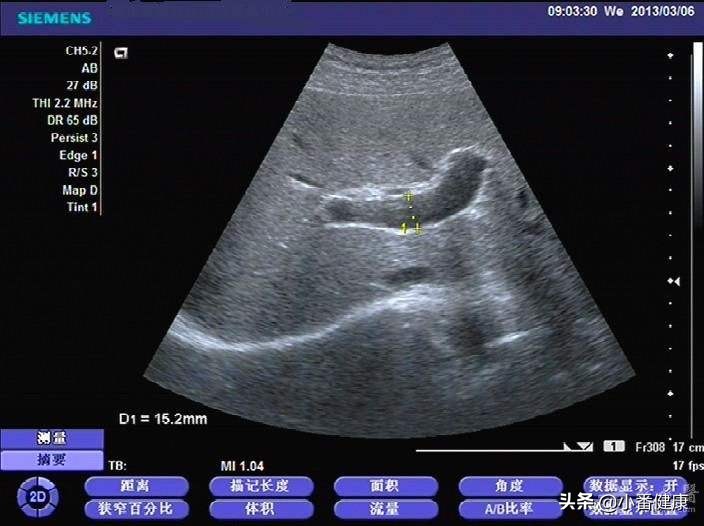

此外,即便身体感觉无任何不适,也最好定期复查一下肝功能,及时了解转氨酶、白蛋白、胆红素等,帮助知道生活饮食是否合理,肝病进展程度等。